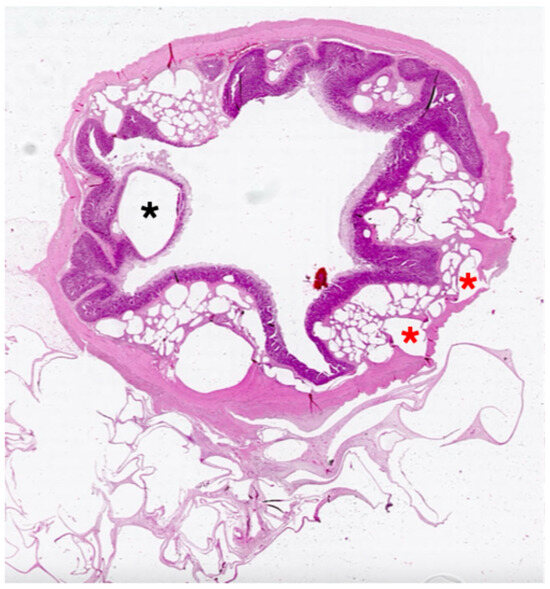

Unveiling Intestinal Emphysema in Pigs: Morphological Insights and Pathogenetic Implications

Intestinal emphysema is a rare pathological condition observed in humans and animals, characterized by the presence of multiple gas-filled cysts within the intestinal wall. In pigs, it is occasionally observed at slaughter, without affecting carcass suitability for human consumption or impairing farm profitability. Despite investigations, the etiology and pathogenesis of intestinal emphysema remain poorly understood. Therefore, this study aimed to provide further morphological insights into porcine intestinal emphysema through histopathological, histochemical and immunohistochemical methods. A total of ten slaughtered heavy pigs were examined, showing gross lesions consistent with intestinal emphysema. Gaseous cysts were predominantly located in the submucosal and mesenteric layers, at least partially lined by lymphatic endothelial cells. The cysts were separated by fibrous connective septa and were almost invariably associated with granulomas, consisting of epithelioid macrophages and multinucleated giant cells. Overall, the immunohistochemical patterns of porcine intestinal emphysema overlap with those described in humans and support the hypothesis that lesions likely originate within the lymphatic vessels. Full article